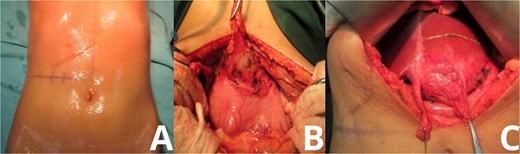

Upon entering the peritoneal cavity, dense adhesions were noted between the round ligament and the lesser curvature of the stomach. Careful dissection revealed a well-encapsulated mass located in hepatic segment 3. The mass was tightly adhered to surrounding structures but was eventually mobilized without injury to adjacent organs. The liver parenchyma was marked, and a formal anatomical resection of segment 3 was performed (Fig. 2).

Intraoperative exposure of intrahepatic gossypiboma. Photographs taken during exploratory laparotomy document the identification and mobilization of the gossypiboma. (A) Initial intra-abdominal view reveals dense adhesions between the round ligament and lesser curvature of the stomach. (B, C) Progressive dissection exposes a fibrous, well-encapsulated mass within hepatic segment 3. The mass is separated from surrounding structures with careful technique, avoiding injury to adjacent organs.

The mass measured approximately 10 cm and, upon resection, was found to contain retained surgical gauze consistent with a textiloma. The rest of the intra-abdominal cavity was explored and found to be unremarkable (Fig. 3).